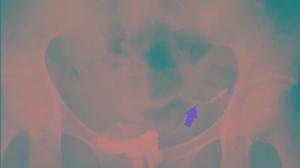

輸卵管造影檢查中的延遲片是判斷輸卵管是否暢通的重要資料。造影檢查為什麼要拍攝延遲片?延遲片一定要在特定的時間內拍攝嗎?沒有延遲片真的不能診斷出輸卵管是否通暢嗎?稍後播出的《袁渭清不孕講壇》將為您解讀《不可或缺的延遲片》。

講座截圖2、醫療規則規定:醫療機構在進行子宮輸卵管造影檢查操作時必須拍攝延遲片。全國醫學院校統編教材最新版7版本科婦產科教材400頁中有明確的規定。不拍延遲造影片是不符合醫療規範的。

子宮輸卵管造影輸卵管造影經X線的子宮輸卵管造影是通過導管向宮腔及輸卵管注入造影劑,利用X線診斷儀行X線透視及攝片,根據造影劑在輸卵管及盆腔內的顯影情況來了解輸卵管是否通暢、阻塞部位及宮腔形態的一種檢查方法。

延遲片延遲片是被用來診斷輸卵管通暢程度的一個重要憑據,也是醫生判斷患者輸卵管是否通暢的主要依據。延遲片是在子宮輸卵管檢查過程中拔除造影導管後拍攝的最後一張造影片。它的醫療原理是依據盆腔內造影劑彌散及輸卵管內殘留情況來確診輸卵管的通暢程度。